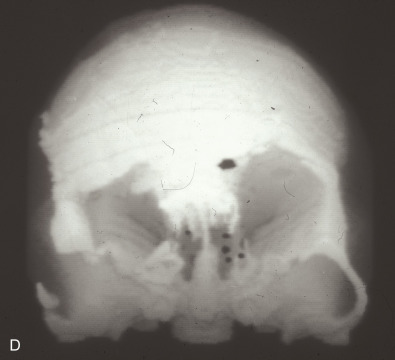

Just before his first birthday this boy was bitten by a Boxer dog and sustained a loss of most of his right parietal bone, dura, and a good bit of parietal lobe ( Fig. 3.1.1 ). Excellent neurosurgical care debrided nonvital brain and repaired the dura with an artificial dural substitute. Because of the lack of native dura, spontaneous regeneration of the bone was unlikely. Three months later, at 14 months of age, a switch cranioplasty was performed, taking the entire left parietal bone to replace what was missing on the right. This left the left side devoid of bone, but with healthy dura and pericranium. Several fragments of his skull, which had been saved and frozen from the original operation, along with a large segment of rBMP-2 impregnated in collagen sponge, were placed between the dura and the pericranium. At 2 years of age the boy had an intact skull and only a mild left hemiplegia.